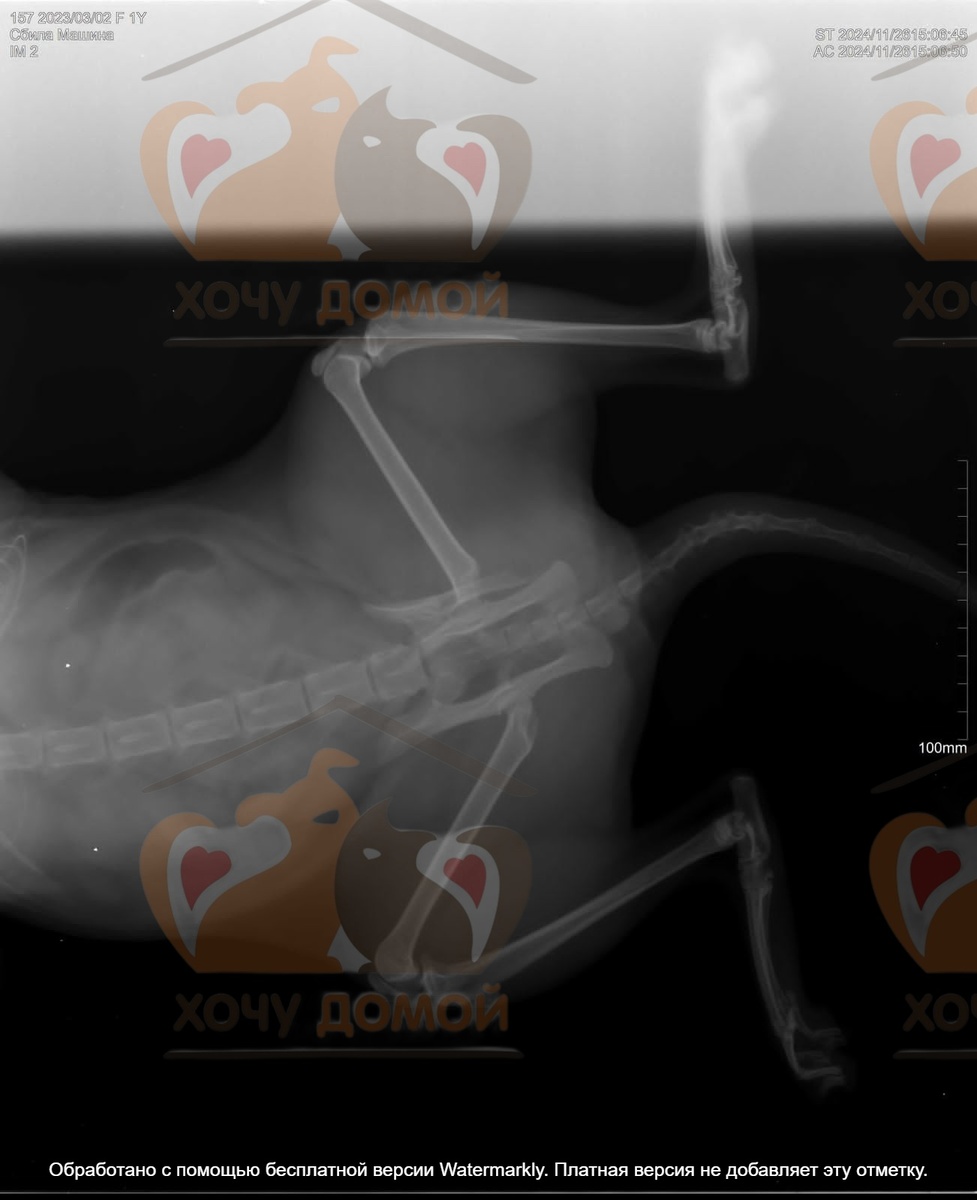

И вот вчера прямо на глазах у людей, когда кошка перебегала дорогу, она попала под машину. В шоке она сначала спряталась за забором, но люди нашли её. Было видно что она сильно пострадала. Тут нужна была неотложная помощь, счет шел на часы. В нашем городе с кошкой были в двух клиниках, к сожалению смогли поставить только диагноз - перелом костей таза. У нас такие сложные операции не делают, к сожалению.

Поэтому пришлось срочно везти бедолагу в соседний город Орёл, в клинику БИО, где уже много лет работает замечательный врач, Кузнецов Д.Г.

Сколько он прооперировал наших животных, не пересчитать, так что кошка в надёжных руках. А нам очень нужна ваша поддержка и помощь с оплатой операции и лечения в стационаре.